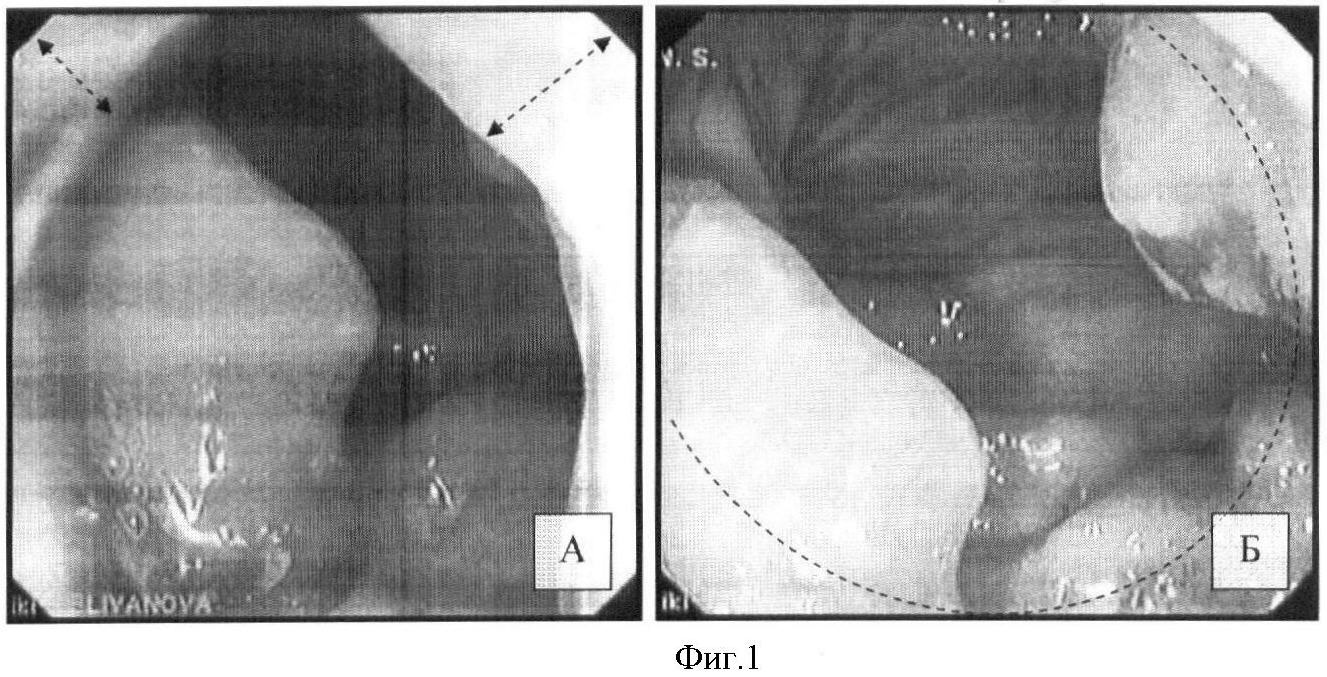

Резервуарография. С помощью контрастной клизмы дистальный отдел ободочной кишки беспрепятственно заполнен барием. Во фронтальной проекции за анальным отверстием определяется зона повышенного давления протяженностью 20-25 мм (фиг.7, А). Проксимальнее данной зоны кишка плавно переходит в резервуар, напоминающий естественную ампулу прямой кишки. Приводящая петля резервуара обычных размеров. В косой проекции между промежностным и тазовым отделами низведенной кишки определяется аноректальный угол, образованный за счет тракции сформированного гладкомышечного лоскута (фиг.7, Б). Величина угла в пределах 120°.

Фиг.7 – проктограммы через 1 год после операции: А – резервуар в прямой проекции; Б – резервуар в боковой проекции; пунктирными линиями выделен резервуарноанальный угол (5) и проекция гладкомышечного лоскута леватора (3).